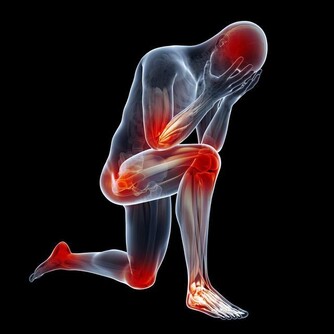

6、發炎

身體為了保全大局,將血液中的病毒和細菌集中在一個地方,因此會出現紅腫熱痛的反應,

我們又消炎吃大量的抗生素,又幫了病毒的忙,身體沒有辦法只能進入第7個階段。